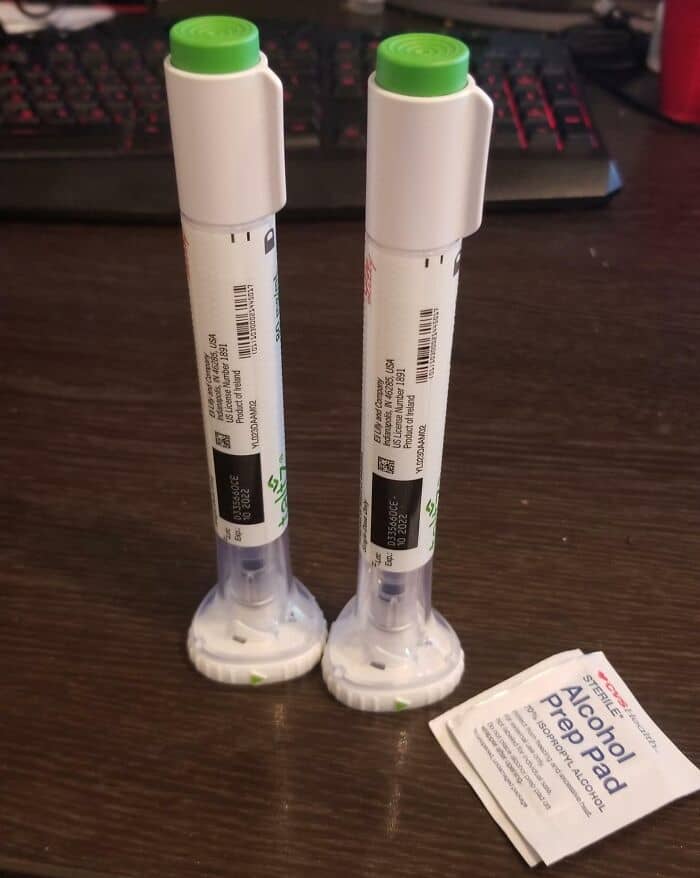

#46 US Healthcare. This Is What $17,000 Looks Like… Insurance Refusing Next One Because I’m “Over Limit”

#47 Each Of These Teeny Pills Costs $40

So glad my family has health insurance, but how do people without health insurance afford medicine in the U.S?

Can’t imagine not having health insurance.